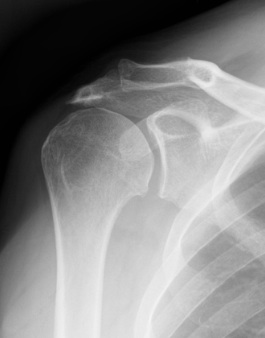

Acromial Morphology

Bigliani / Assess on Supraspinatous Outlet View / Scapula Lateral

| Type 1: Flat | Type II: Curved | Type III: Hooked |

![]() |

Andrea et al Skeletal Radiol 2024

- 850 patients with suspected shoulder impingement

- type III in 16%

- meta-analysis of acromial morphology and rotator cuff tears

- type III acromial spurs associated with rotator cuff tears

- type I and II are not

Type III acromial spur associated with a full thickness rotator cuff tear